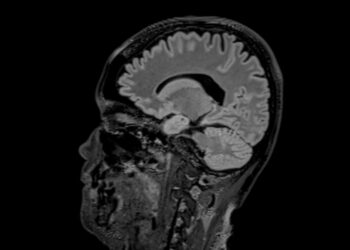

Skaityti daugiauDetailsKearns-Sayre sindromas – reta neuromuskulinė liga, dažniausiai pasireiškianti jauname amžiuje. Šis sindromas veikia ne tik akis, bet gali apimti ir...

Skaityti daugiauDetailsKawasaki liga – reta liga, sukelianti kraujagyslių uždegimą (vaskulitą), kuri dažniausiai paveikia mažus vaikus. Uždegiminės ir pažeistos kraujagyslės gali susiaurėti,...

Skaityti daugiauDetailsKallmano sindromas – tai retas genetinis sutrikimas, kuris lemia lėtą arba neįvykstantį lytinį brendimą ir dažnai paveikia uoslės pojūtį. Jo...